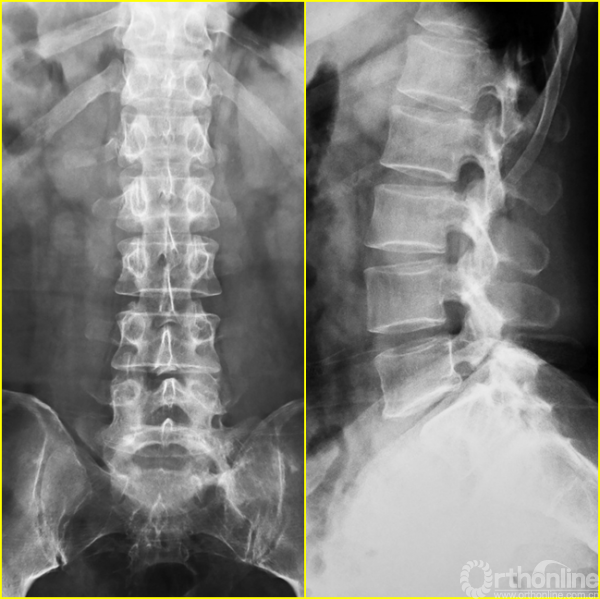

腰5椎体前滑脱I-II°,峡部裂,动力位显示腰5-骶1节段明显失稳